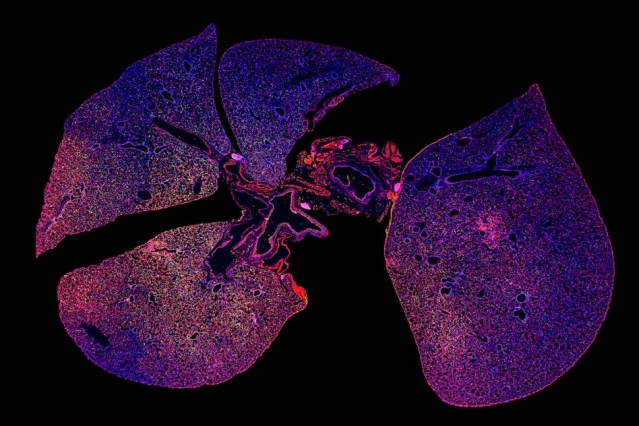

bacterial pneumonia